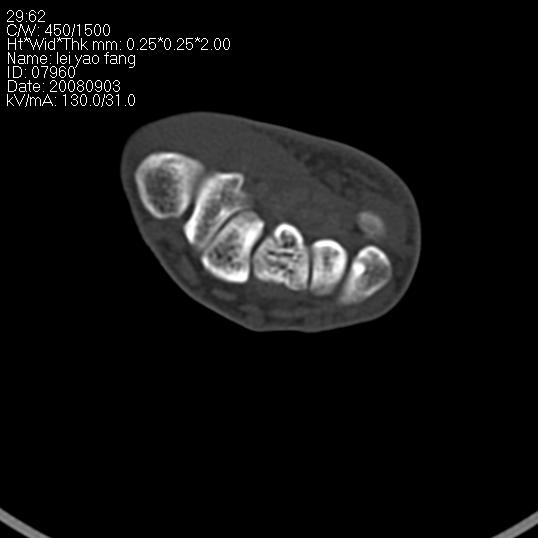

以下是引用杀毒软件在2008-9-4 17:41:00的发言:[br]考虑----舟骨囊肿